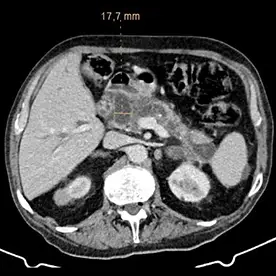

Durchführung einer kontrastmittelgestützten CT-Untersuchung des Abdomens in arterieller und venöser Kontrastmittelphase. Neben einer reizlosen Cholezystholithiasis zeigt sich ein massiv erweiterter D. pancreaticus bis zur Papille und diffuse zystische Pankreasläsionen, teils mit Verkalkungen (Bild 4 und 5) mit dem Hauptbefund im Pankreasschwanz angrenzend an die linke Nebenniere; kein Nachweis solider Anteile (Bild 1). Zusätzlich wurden mehrere kalkdichte Konkremente im Pankreas nachgewiesen, die sich vorwiegend im Bereich des Caput befinden. Keine Lymphadenopathie. Keine metastasensuspekten Herdsetzungen. Als weitere Nebenbefunde wurden eine parenchymverschmälerte Niere rechts und der V.a. auf ein Nebennierenadenom geäußert.

Verdacht auf eine intrapankreatische muzinöse Neoplasie (IPMN) vom Hauptgangtyp. Auch die intra- und extrahepatischen Gallenwege zeigen sich deutlich dilatiert (Bild 2 und 3).